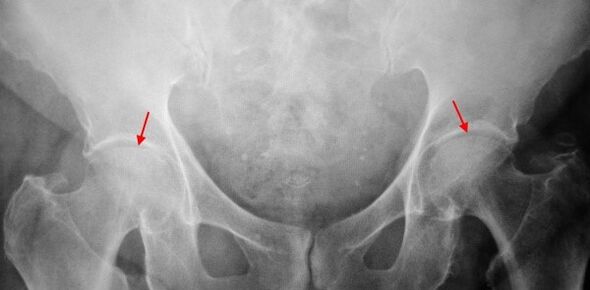

On X-rays of patients with primary binary bovine car, slight changes were identified: uneven stenosis of joint spaces, and the growth of bones around the outer or internal edge of the acetabular without changes in the head and neck of the femoral head.

Binary images used in X-ray images for secondary binary binary images, identifying obvious uneven stenosis (more than normal height) in joint gaps.The femoral head moves upward to some extent, deformation and size increase, and the contour becomes uneven.The bone growth of the sacrificial neuropathy appears not only inside, but also on the outer edge of the acetabular and then goes out of the cartilage.

Regarding the third degree of transverse bow radiography, the sharp narrowing of the joint gap, the significant expansion of the thigh head and multiple bone growth were detected.

Competitive diagnosis is based on clinical signs and data from other studies, mainly XhRography.In many cases, X-rays can establish not only the extent of corona but also the cause of it.Thus, for example, an increase in the cervical cross-sectional angle, acetabular scene and flattening suggest that changes in the proximal part of the femur suggest that Coksartrosis is the result of Pertes disease or young epidermal decomposition.Changes can also be detected on X-rays of patients with laparotomy, indicating injury.